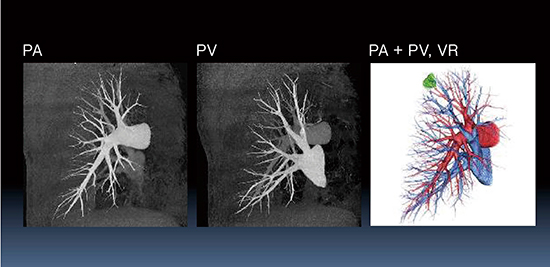

この点を考慮して作成した当院の肺動脈(PA),肺静脈(PV)分離造影法の撮影プロトコルを図1に示す。本法で撮影することによって,PAとPVがきわめて良好に分離でき(図2),PA相のデータから肺血流量(PBV)が測定可能となる。

図1 当院のPA,PV分離造影法の撮影プロトコル

図2 図1のプロトコルで得られたPA,PV分離画像